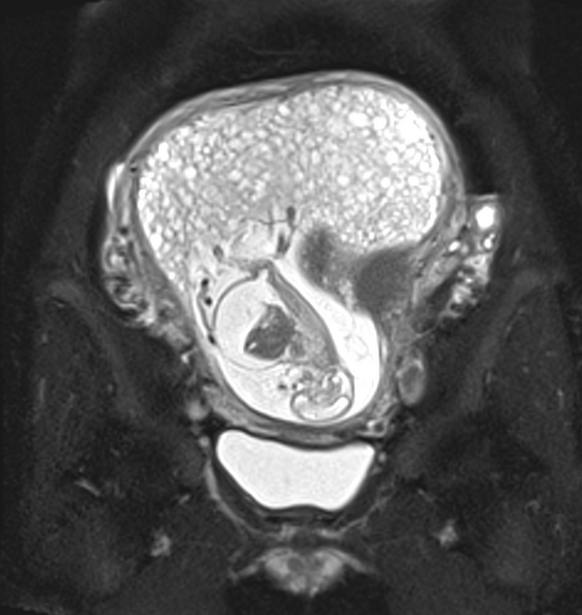

complete mole과 partial mole의 차이 (포상기태, Hydatidiform mole)

정자와 난자가 잘 만나는 것이 항상 쉬운 것은 아니다. 비정상적인 결합이 일어나면 때때로 포상기태(Hyda...